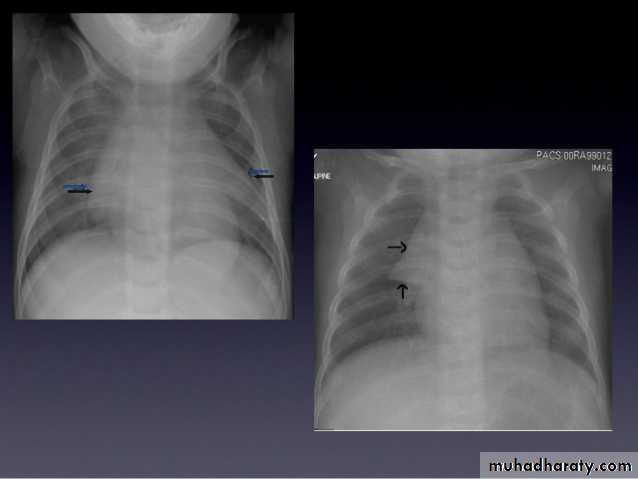

Lobular consolidation ( broncho pneumonia )

Very important to consider that pulmonary edema in normal sized heart have close similar appearance to broncho pneumonia

The important Golden Key differentiation is the cardiac size being enlarged in pulmonary edema .

Interstitial pulmonary edema

Pulmonary edema ( alveolar pulmonary edema)

Bat wing sign ( alveolar pulmonary edema)

36.lobuler consolidation (lobular pneumonia )37.discussion

38.interstial pulmonary edema

39.pulmonary edema ( alveolar pulmonary edema )

40.batwing sign ( alveolar pulmonary edema )